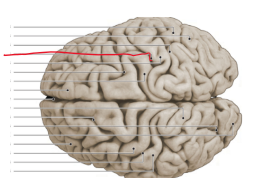

sulcus centralis

fissura longitudinalis cerebri